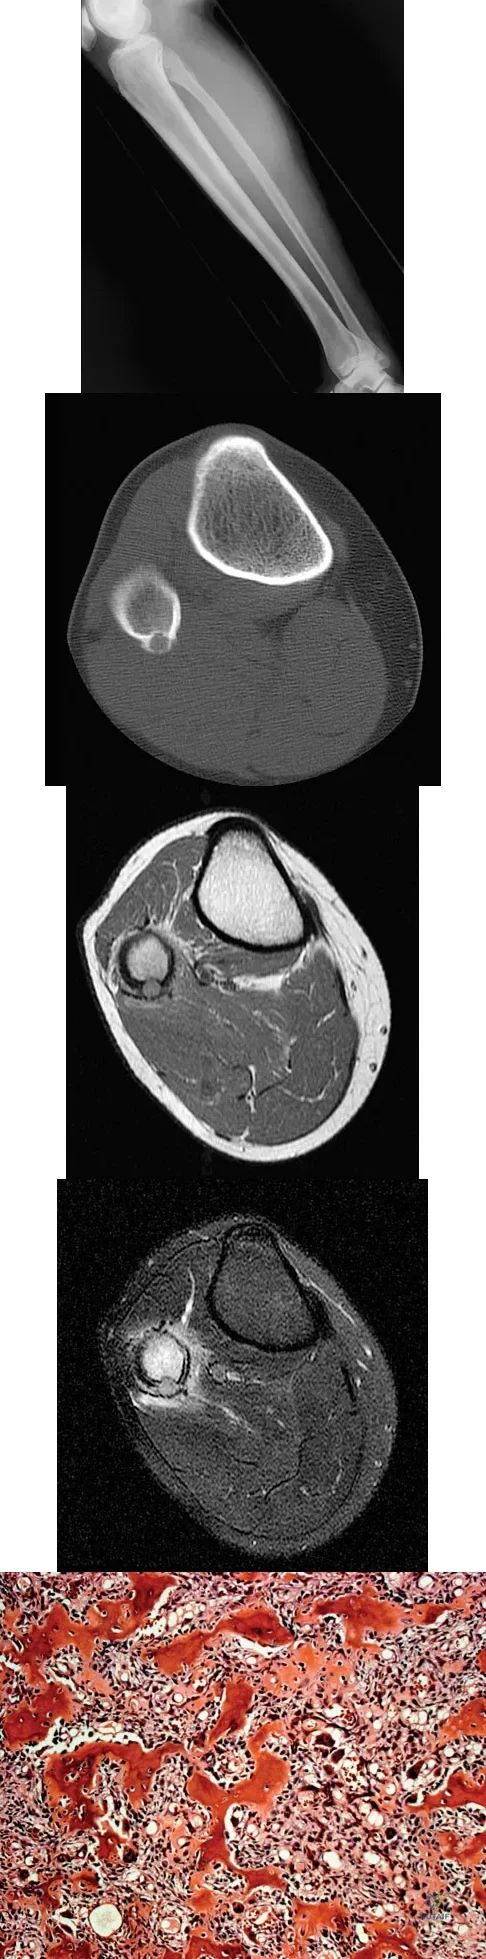

A 23-year-old man has had right posterolateral knee pain and occasional lateral calf dysesthesias for the past 8 months. A radiograph, CT scan, MRI scans, and a biopsy specimen are shown in Figures 62a through 62e. What is the most likely diagnosis?

The radiograph shows an eccentric, cortically based lytic lesion in the proximal fibula. The CT and MRI scans confirm that it is well circumscribed and cortically based with significant surrounding edema. The radiographic differential diagnosis would be a Brodie's abscess or osteoid osteoma. An osteoblastoma would have to be greater than 2 cm in size. A chondroblastoma may also have significant edema around it, but it is an epiphyseal-based lesion, not cortically based. The well-circumscribed nature of the lesion is not consistent with osteosarcoma. The pathology shows a very cellular and vascular stroma with plump, but not atypical osteoblast cells making a matrix of immature woven bone. There are no abundant inflammatory cells or dead bone suggestive of osteomyelitis or a Brodie's abscess. Therefore, the clinical and histologic picture is most consistent with an osteoid osteoma. Percutaneous radiofrequency ablation, usually with CT guidance, has become the preferred method for treating most cases of osteoid osteoma. Rosenthal DI: Radiofrequency treatment. Orthop Clin North Am 2006;37:475-484.